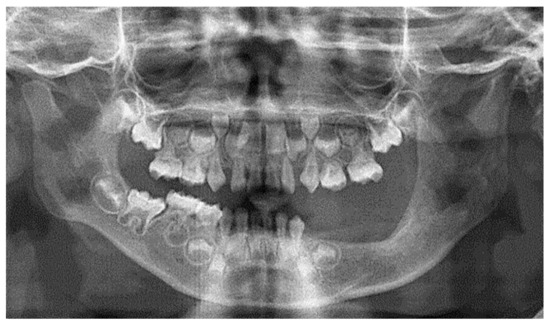

2.1. Clinical and Preoperative Radiological Presentation